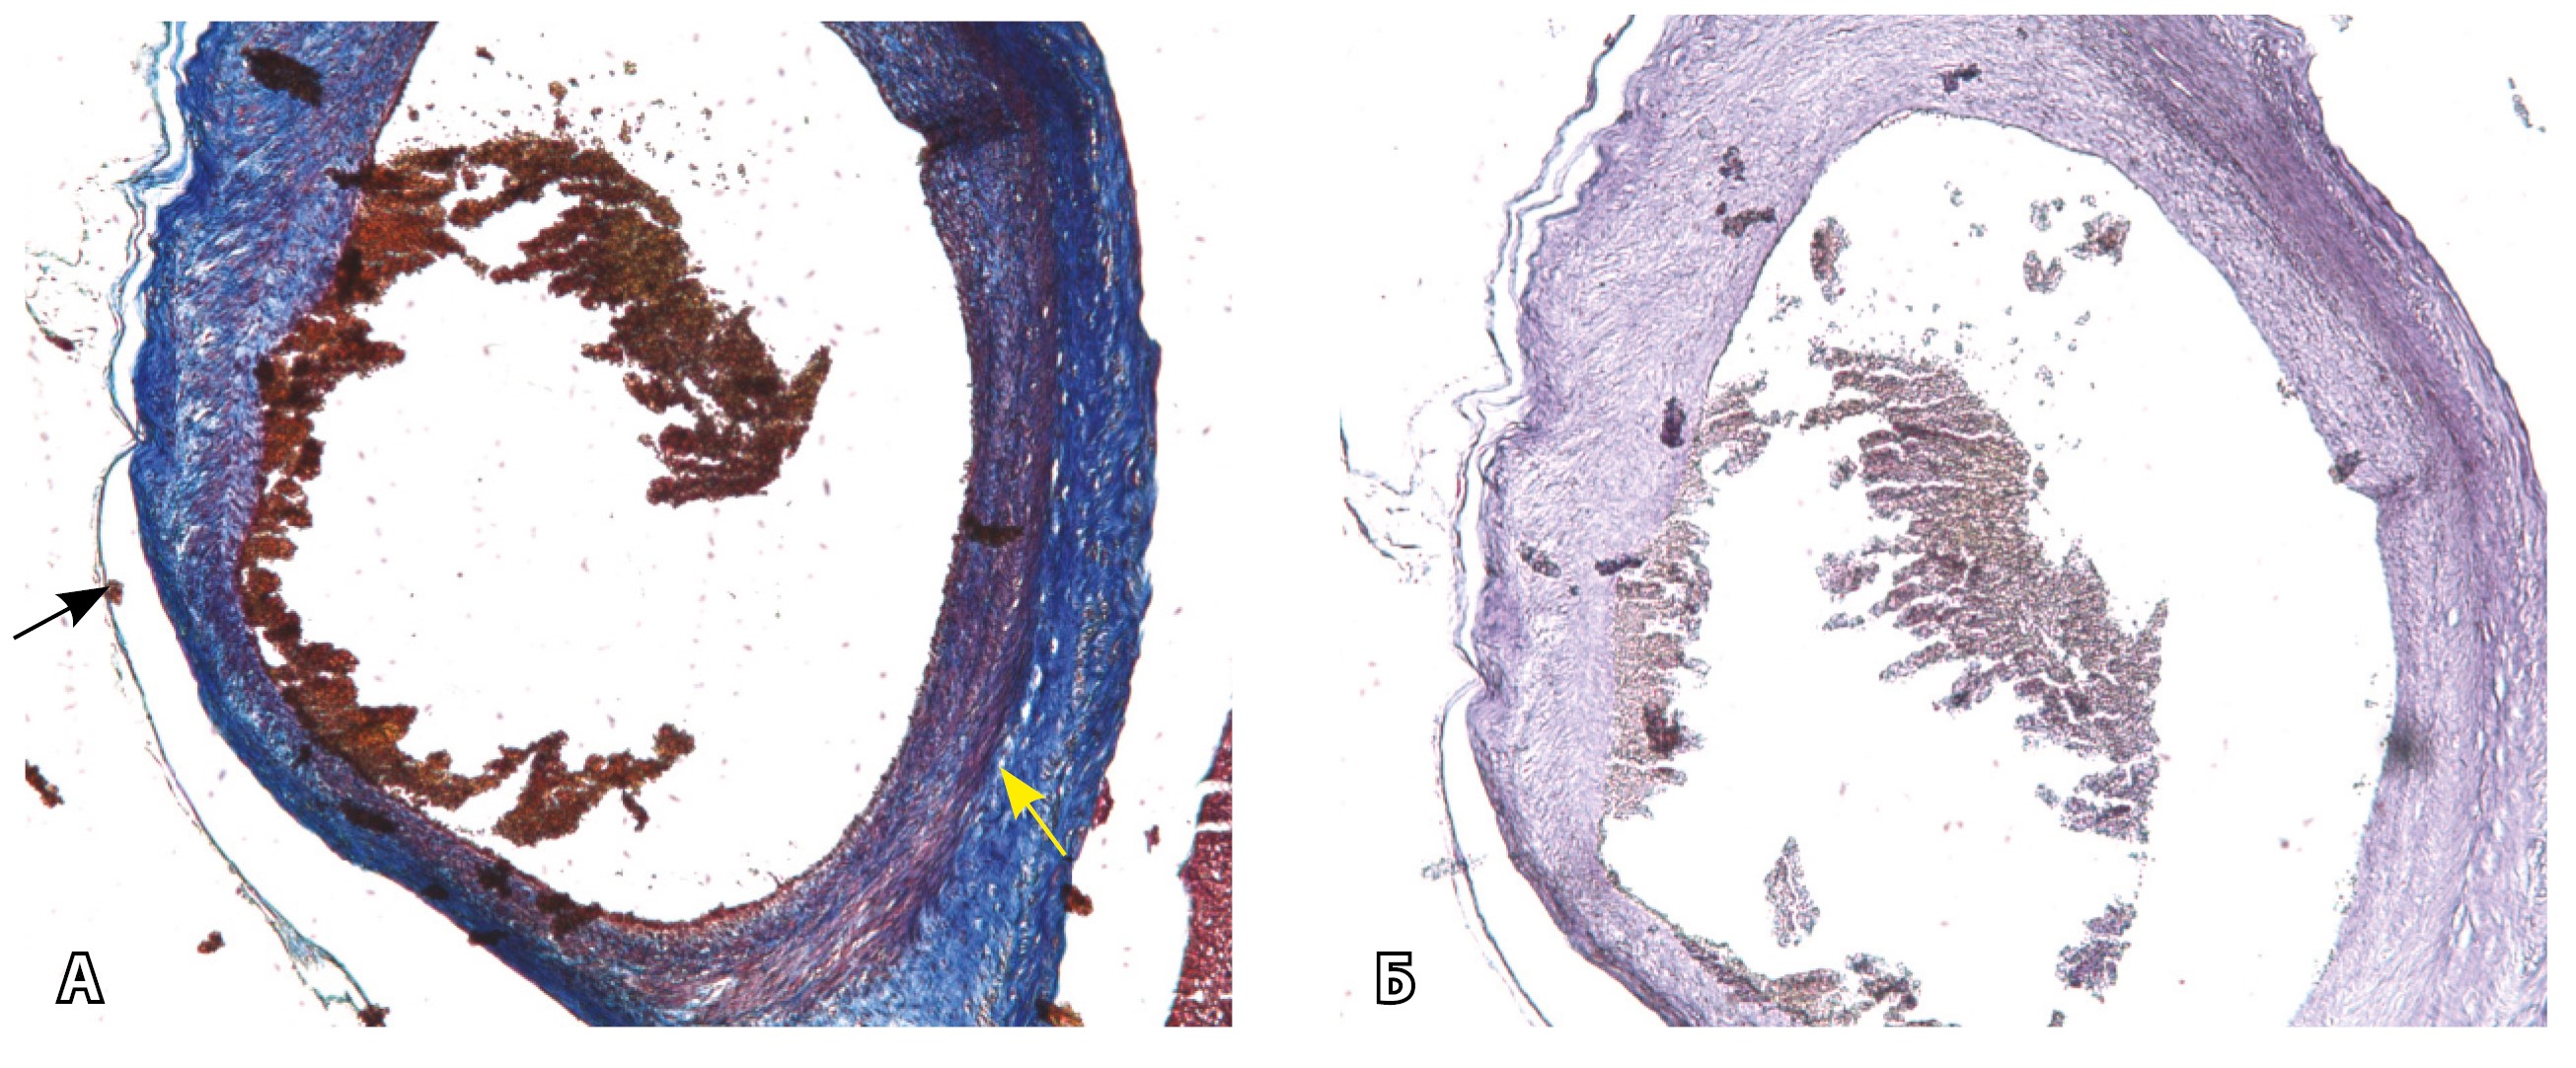

Рис. 13. Самые крупные сосуды в пределах серозной оболочки стенки матки: А, Б – серийные срезы артерии; × 50. При окраске по Маллори (А) видна тонкая полоска мезотелия (черная стрелка), слабо дифференцированная мышечная стенка артерии, вокруг нее – плотная коллагеновая оболочка (желтая стрелка), в просвете определяются тромботические массы. При окраске по Вейгерту (Б) наблюдается полная потеря внутренней и внешней эластических мембран

Эластический каркас представлен сетью тонких волокон, без концентрации на внутреннюю и внешнюю мембраны. Однако маркер СD34 констатирует сохранение эндотелия, что свидетельствует о том, что по артериям циркулирует кровь, не сворачиваясь (рис. 13).

На микропрепаратах васкуляризация серозной оболочки представлена множеством крупных сосудов, идущих в разных направлениях и анастомозирующих друг с другом. Возможно, имеются артериовенозные соустья. На серийных срезах также видно, что в стенках артерий трудно различимы два слоя миоцитов (продольный и поперечный). Со стороны адвентиции они окружены толстым «футляром» из грубоволокнистой голубой ткани (при окраске по Маллори). Она проникает в стенку артерий, замещая мышечный слой (рис. 12).

Рис. 12. Истончение миометрия; в составе серозной оболочки видна крупная артерия, окруженная плотной соединительной тканью. А – cосуды в составе серозной оболочки (окраска по Маллори; × 200), не дифференцированная на мышечные оболочки стенка артерии, справа – вена, оба сосуда покрыты фиброзной оболочкой, внизу виден слой мезотелия в составе серозной оболочки; Б – серийный срез тех же сосудов при окраске на выявление эластических волокон, сосуд с соединительнотканной муфтой (окраска по Вейгерту; × 50): определяется полная дезорганизация эластичного материала в стенке; стрелкой указан мезотелий (аналог pl. increta, PAS 2 по FIGO)